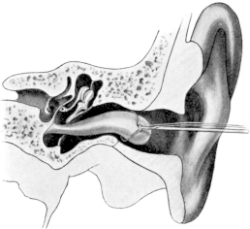

| 174. | Examination of the Ear | 307 |

| 210. | Passing the Eustachian Catheter | 365 |

| 211. | Passing the Eustachian Catheter | 365 |

| 212. | Passing the Eustachian Catheter | 366 |

| 213. | Passing the Eustachian Catheter | 366 |